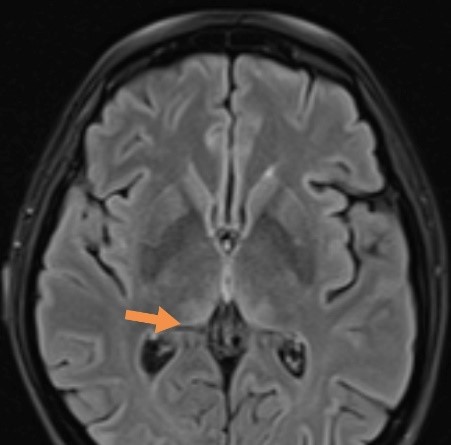

MRI of brain was obtained using postcontrast sequences with sagittal and axial T1, axial T2 and FLAIR and diffusion weighted imaging (DWI). On T2/FLAIR sequences there were hyperintensities in the medial part of both thalami and periaqueductal areas (Figure 1), which also showed DWI restriction – highly suggestive for of Wernicke´s encephalopathy (Figure 2).

| Figure 1. Presentation of hyperintensities in thalami and periaqueductal areas on MRI brain in T2/FLAIR sequence. | |